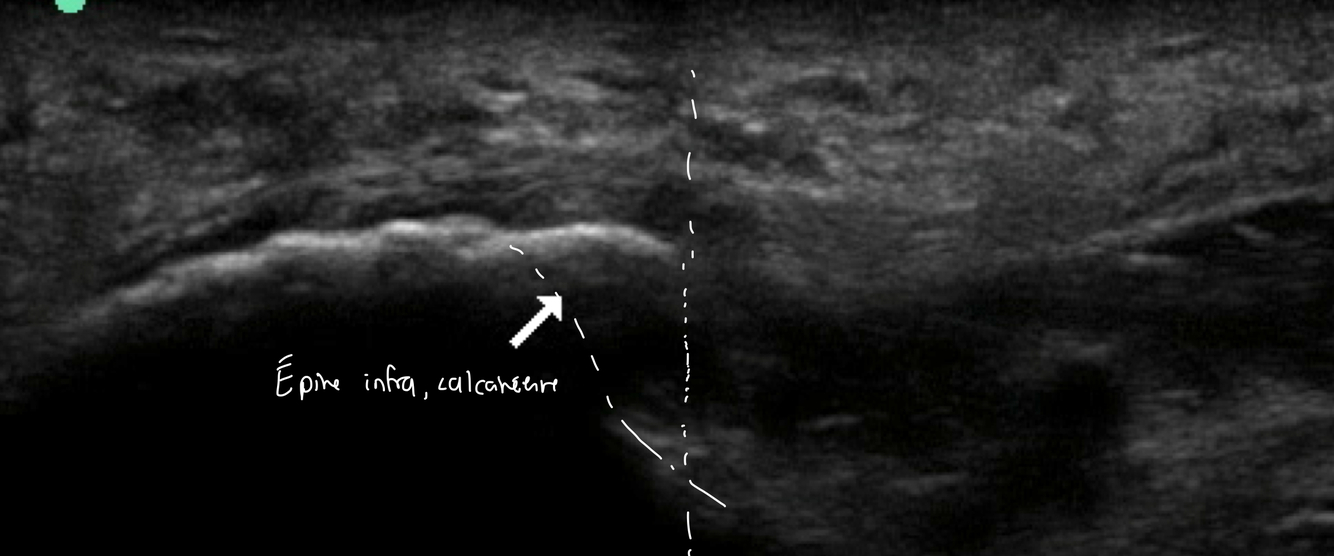

Identifie la pathologie ici

Nous somme en plantaire du pied

Épine infra calcanéenne